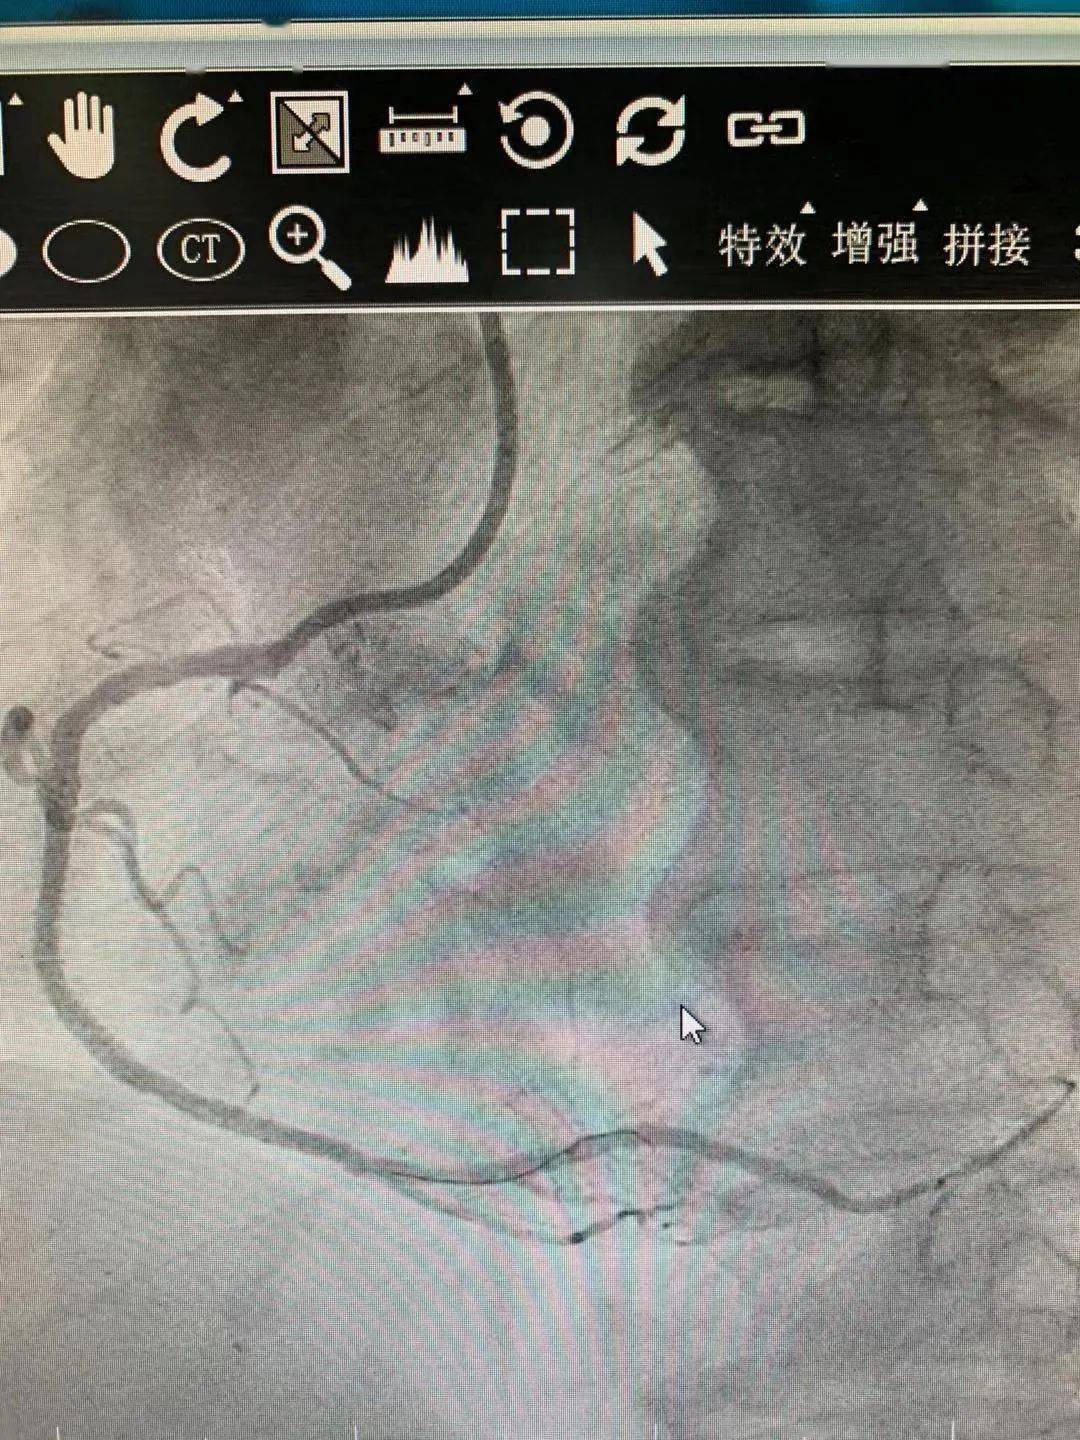

图6 手术后及第4个月随访右冠状动脉近端血管造影及局部血管内超

图片尺寸883x421